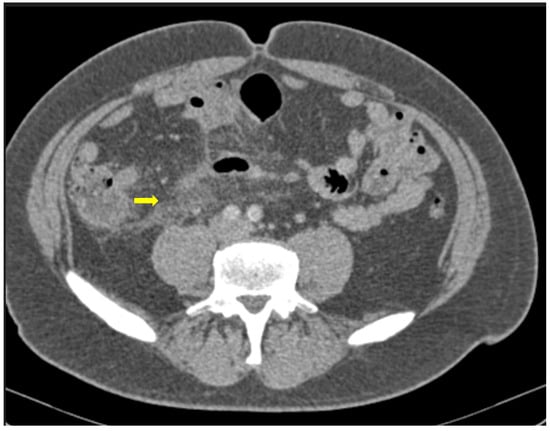

Figure 3. 55-year-old male patient with COVID-19 pneumonia with right lower quadrant pain. CT on admission demonstrating a thickened appendix and proximal fat stranding (yellow arrow), indicating acute appendicitis.